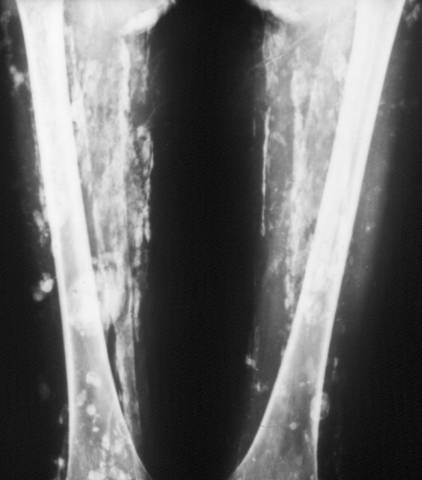

Calcinosis Universalis-Dermatomyositis